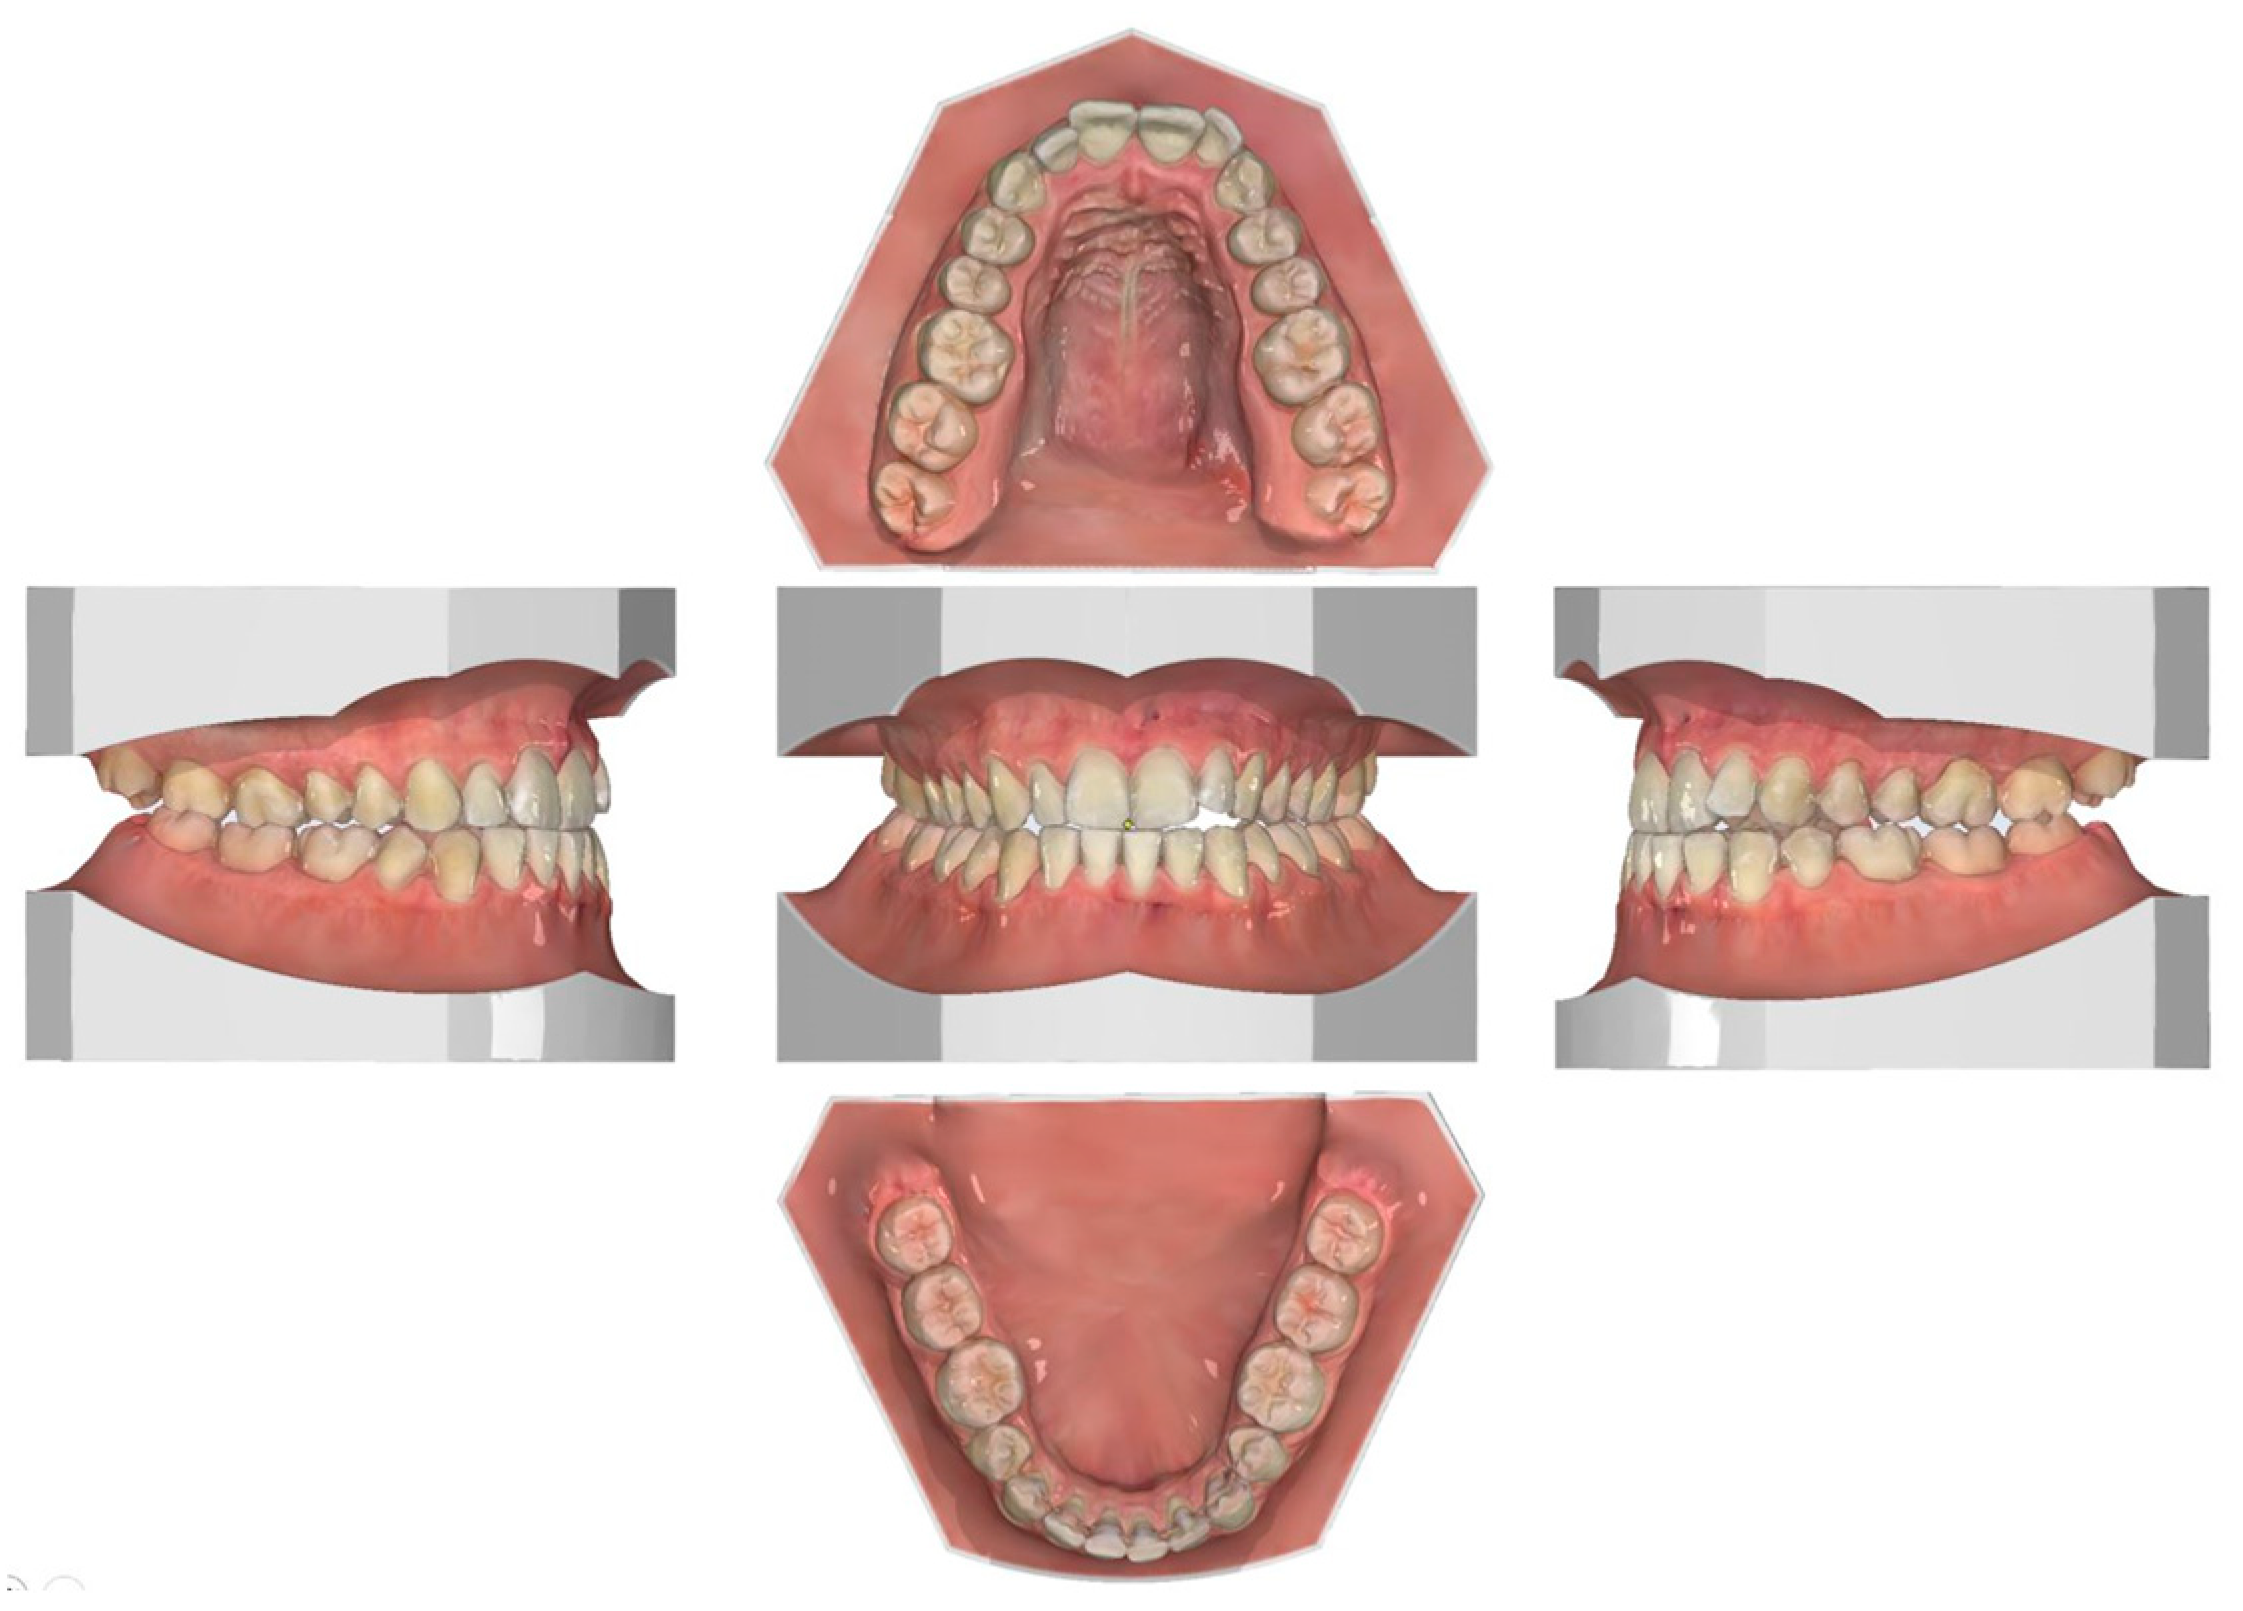

2.1. Diagnosis and Individual Treatment Planning

2.2. Clinical Preparations

2.4. Post-Operative Orthodontic Phase